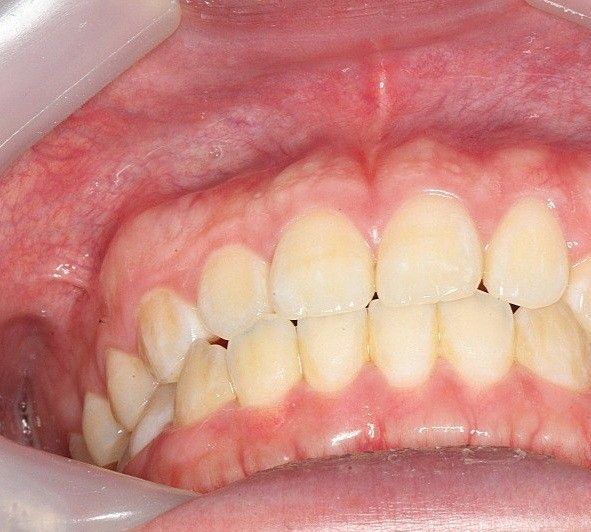

윗니가 앞으로 나오는 정도는 사람마다 다릅니다. 지금 사진상으로 보아 윗니가 앞으로 나온 양이 조금 적어 보이나

정상 범위입니다. 다만 오른쪽 작은 앞니(측절치)는 아랫니가 앞으로 나온 반대교합 입니다.

앞니 교합이 좋진 않으신거 같습니다. 왼쪽치아들은 그래도 잘 물리는데 오른쪽 치아들의 교합이 좋진 않네요.